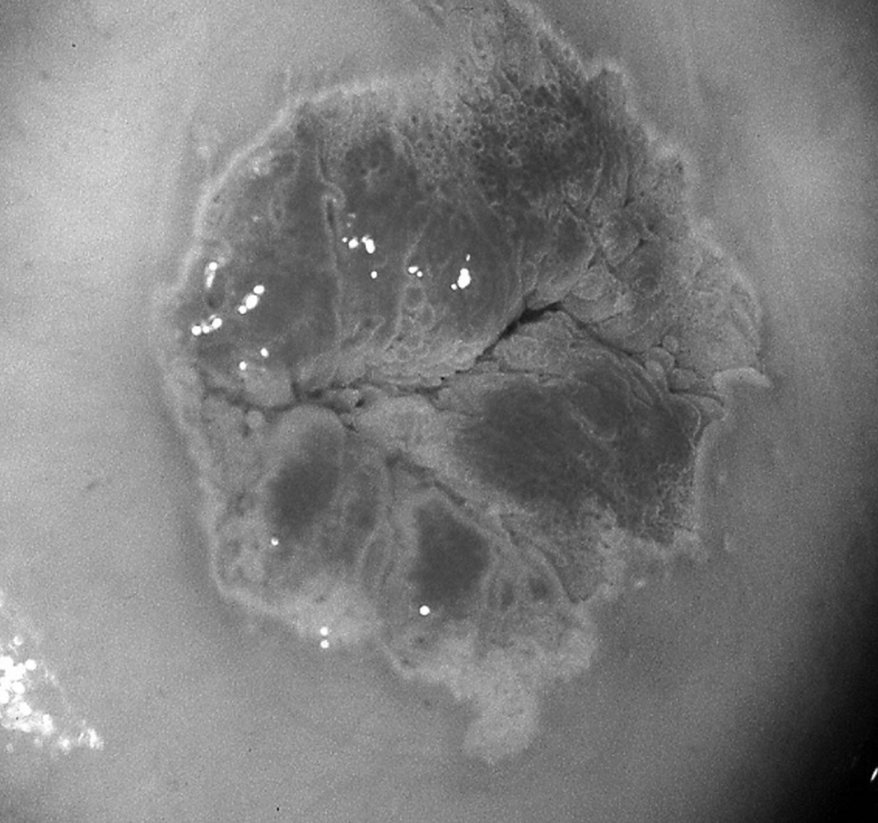

Figure 18.8 Jonction squamo-cylindrique visible à la colposcopie après application d’acide acétique.